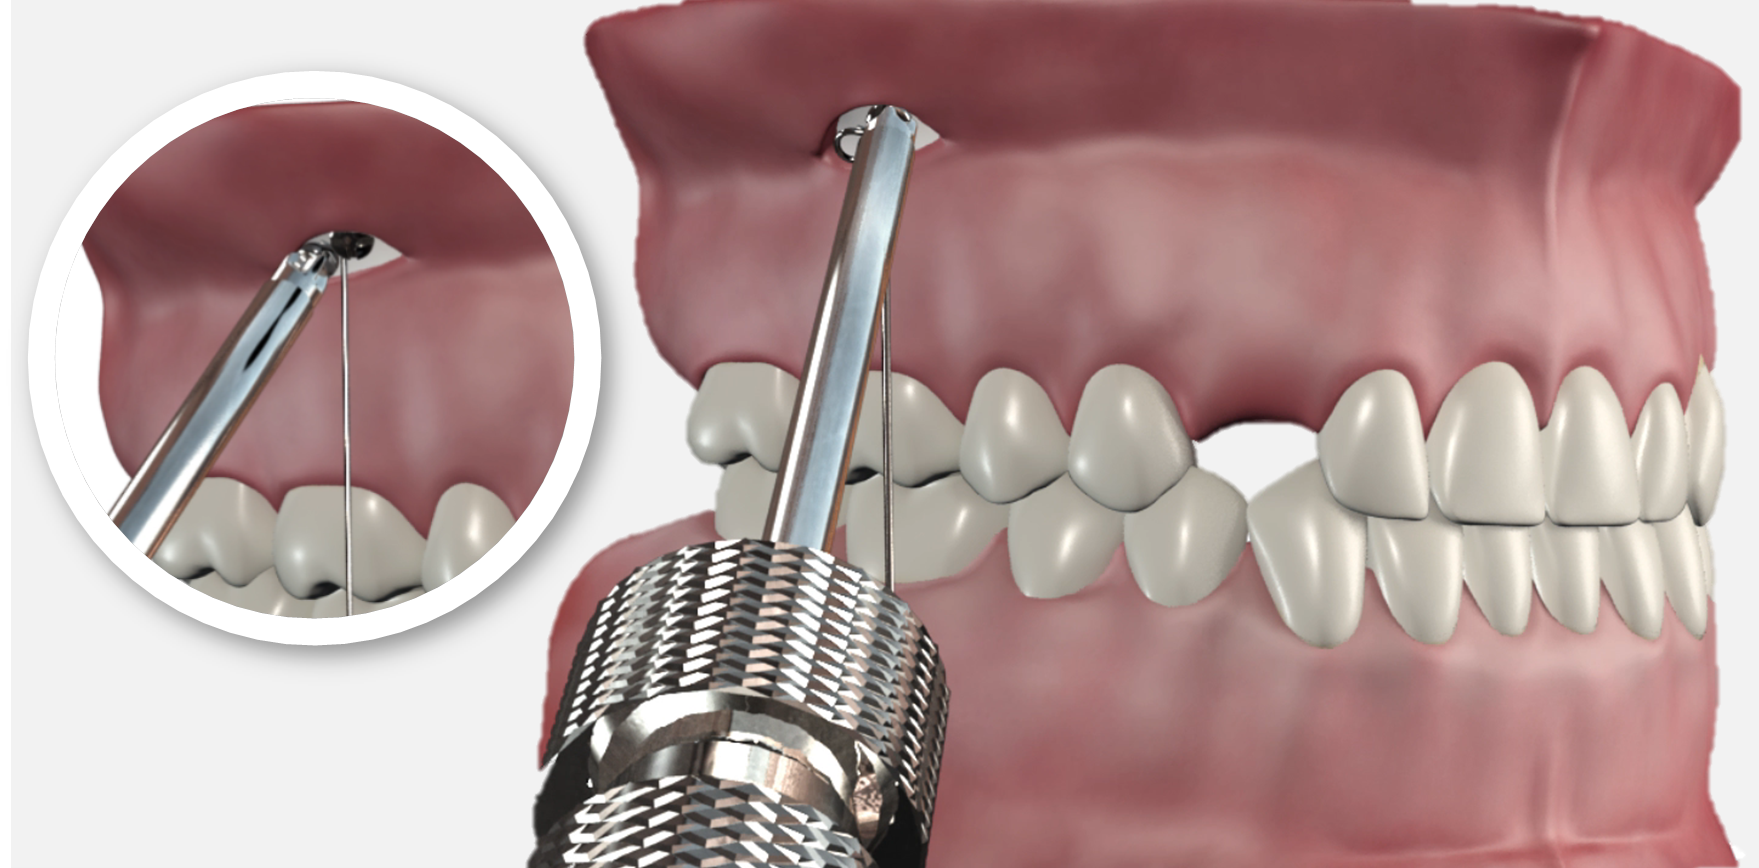

Instrument à baïonnette

- Développé spécialement pour le Système CT8, il permet de réaliser le pli d'émergence de la connectique, appelée baïonnette, au niveau du trait d'incision d'un seul mouvement

- La forme de la fente ont en effet été optimisés afin de réaliser aisément ce pliage

Elle est réalisée à l’aide de l’instrument dédié dont la gorge coiffe le fil et qui est tourné d’ un huitième à un quart de tour environ afin de compenser l’épaisseur de muqueuse.